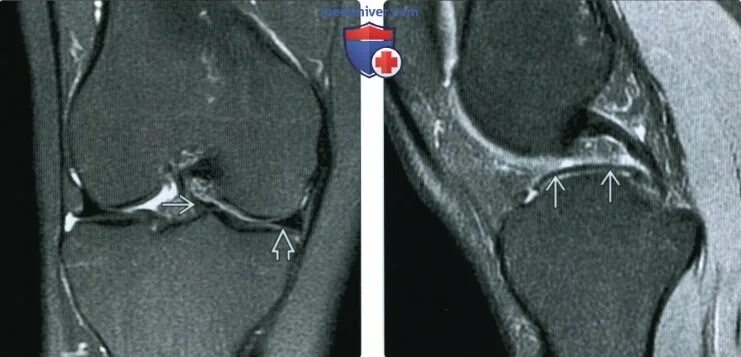

Повреждение мениска мрт